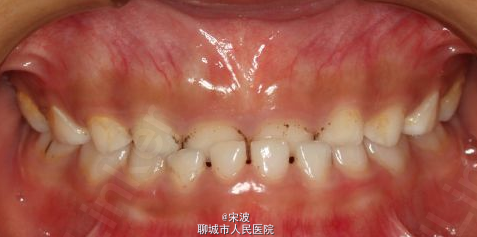

下颌斜面导板HE垫矫治器

适用于上颌比较敏感,有些甚至上颌不能取模型的患者。

下颌联冠式斜面导板矫治乳牙反合